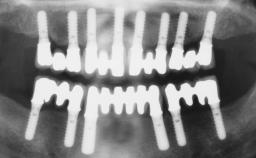

Iliac-Crest Block for Vertical and Horizontal Space Filling in the Anterior Maxilla

A 31-year-old man presented to our clinic 30 days after a motor vehicle accident in which he had suffered a dentoalveolar fracture in the anterior maxilla, including avulsion of teeth 12 and 11 and luxation of tooth 21. He was first treated on the night of the accident in a small city hospital with no oral and maxillofacial surgeon on the staff. A wired retention had been applied and the teeth repositioned to the best of the clinicians’ abilities. When he first presented to our care, the patient showed extrusion of teeth 12 and 11 associated with gingival recession due to bone loss in the anterior maxilla, and the stainless steel wires were still present.

# of Implants 3

Type of Implants One-Piece|Reduced-Diameter

Bone Augmentation Horizontal|Staged|Vertical

Augmentation Materials Autogenous chips|Autogenous block(s)